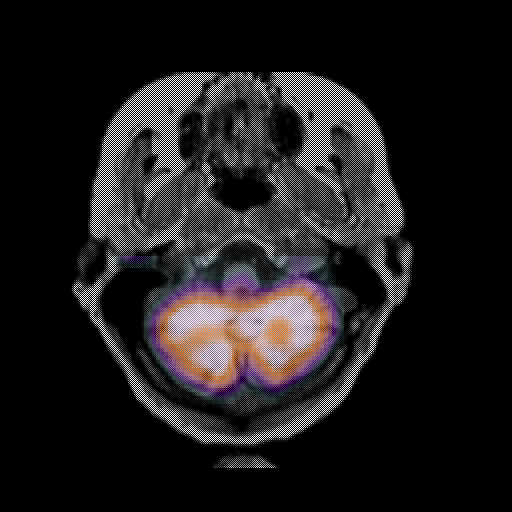

overlay: Slice 9

Slice 9

MRCBFCBF with

T1PDT2T1PDT2